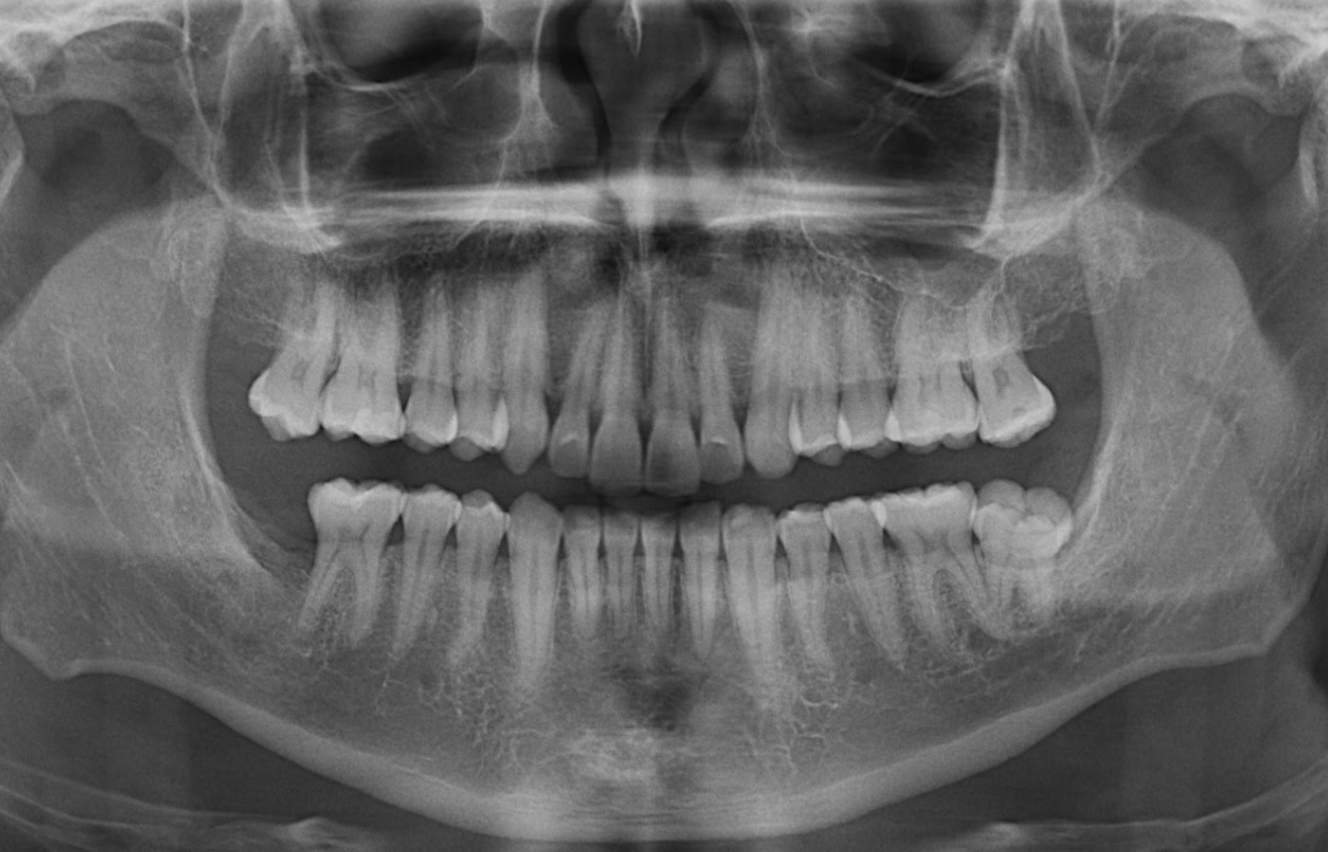

Radiografia Panorámica

A la evaluación de la radiografía panorámica se observa la neumatización de ambos senos maxilares, presencia de placa cervical mineralizada, pérdida de estructura coronaria incisal en piezas anterosuperiores y anteroinferiores y la restauración oclusal de la pieza 37.